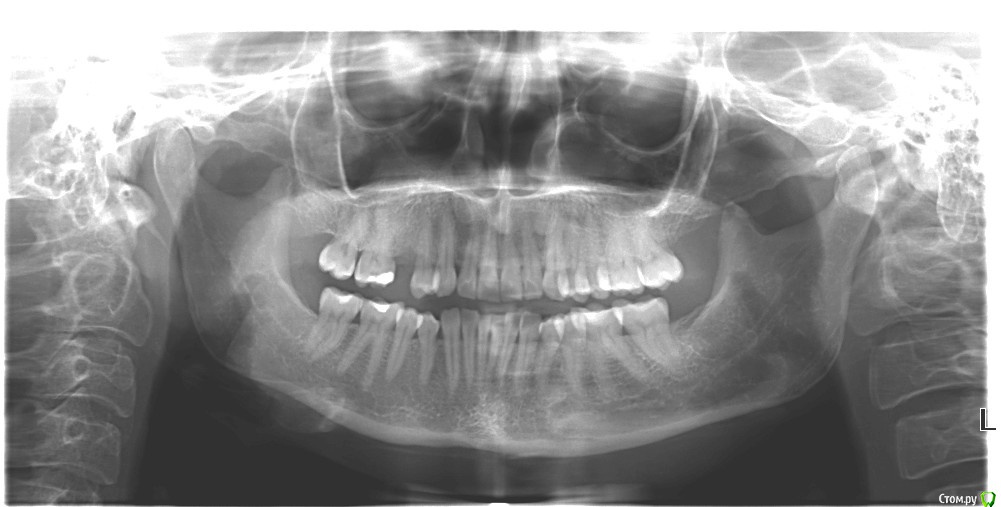

Dashik Опубликовано 9 мая, 2019 Автор Поделиться Опубликовано 9 мая, 2019 Есть снимок только 2-летней давности, прикрепляю ниже. После операции никаких снимков не делалось, врач сказал, что нужно будет сделать через 2 месяца. 1 1 Ссылка на комментарий

red_butler Опубликовано 9 мая, 2019 Поделиться Опубликовано 9 мая, 2019 Сделайте прицельный снимок Ссылка на комментарий

Dashik Опубликовано 16 сентября, 2019 Автор Поделиться Опубликовано 16 сентября, 2019 Добрый день, уважаемые стоматологи!Имплантация проводилась 5 месяцев назад без 3 трех дней. До сих пор хожу с заглушкой, мой врач не спешит продолжать лечение. Сегодня сделала снимок имплантата.Хотелось услышать ваше мнение, и ответы на вопросы, заданные вначале темы.Заранее спасибо! Ссылка на комментарий